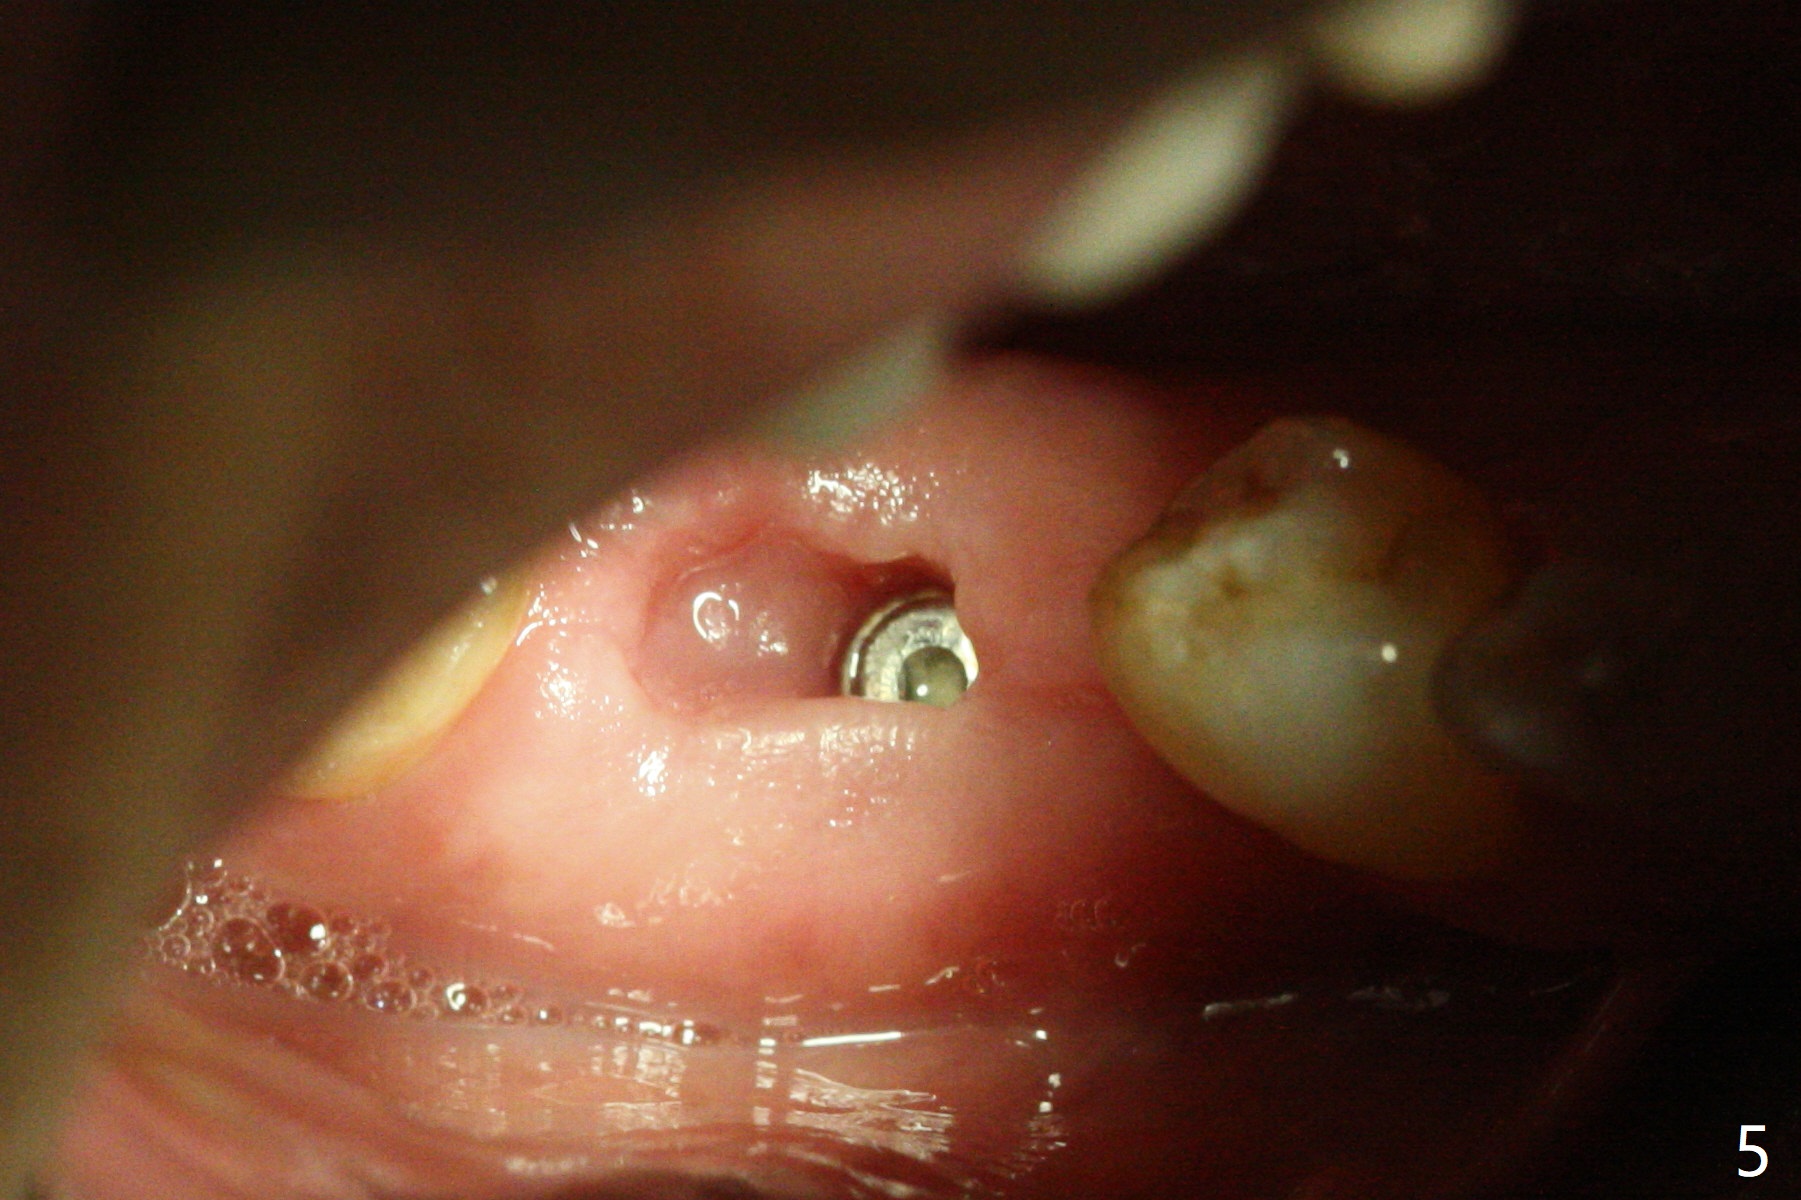

Because of severe pain, block anesthesia is administered prior to extraction. The mesial socket of the tooth #30 is deep with granulation tissue. A 4.5x10 mm dummy implant is placed with < 40 Ncm following sequential osteotomy until 4x13 mm over the septum (Fig.1 (low density)). After 4.5x13 mm drill, a 5x10 mm dummy implant is inserted with <40 Ncm (Fig.2). Since the Inferior Alveolar Canal is invisible (Fig.1,2 (pan should have been taken)), a 5x11.5 mm implant is placed with <20 Ncm. When a 6.5x5.5(3) mm abutment is placed, the underlying implant is turned (Fig.3). With collagen plug is placed in the distal socket and Vera graft around the implant, an immediate provisional is fabricated and relined. When it is seated, it has mobility. In fact the provisional should be locked into the edentulous area while it is malleable. To prevent low primary stability, osteotomy should be under prep, since the implant (red circle) contacts only two bony surfaces, i.e., the mesial (M) and distal (D) walls of the mesial socket (Fig.4 (occlusal view) black oval). There are gaps buccally (B) and lingually (L). In case of low stability, a healing screw or abutment should be placed; the remaining socket is closed with suture. The provisional is loose 19 days postop; it is removed by sectioning. A healing screw is placed. Twelve days later, the wound heals (Fig.5). The patient returns for uncover 8 months postop; although the implant has osteointegrated apparently, the crestal bone resorbs to the implant plateau level (Fig.6 arrow). It seems that the immediate implant should be routinely placed 2-3 mm deeper. The open margin is closed with composite when the abutment/crown is removed after cementation (Fig.7).